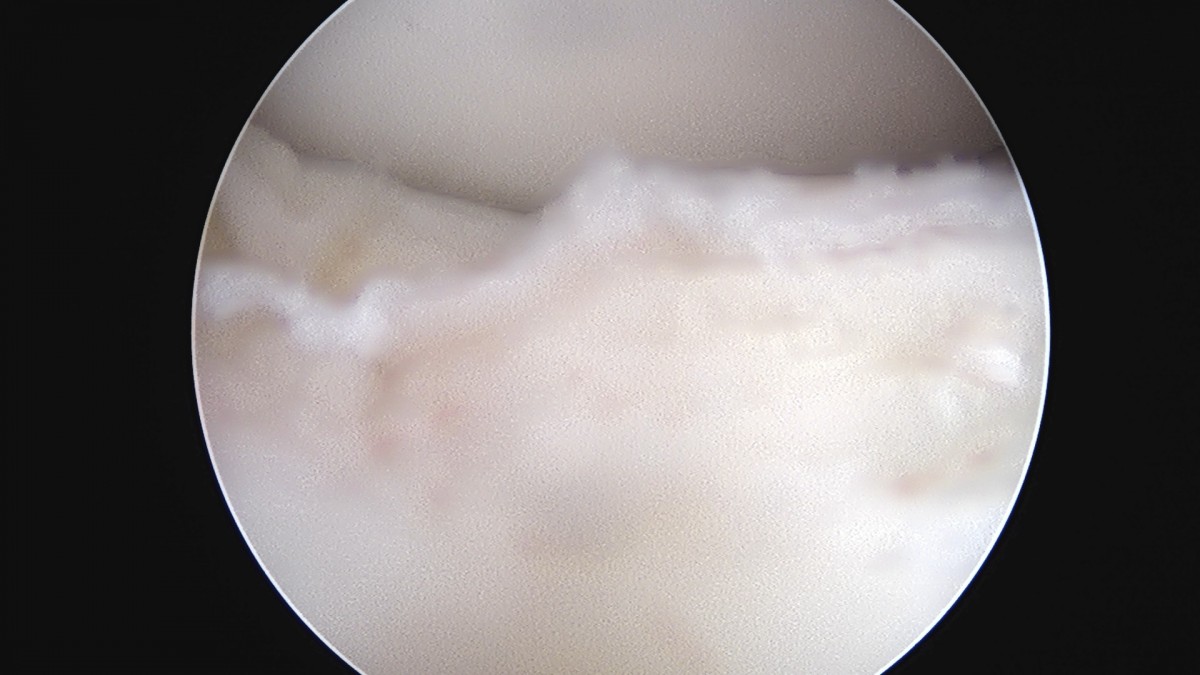

이재상원장님 무릎 반월상 연골판 절제술 김건O 환자

dae765e4d9ac96aee867c9d6292d8784_1758006494_6445.jpg